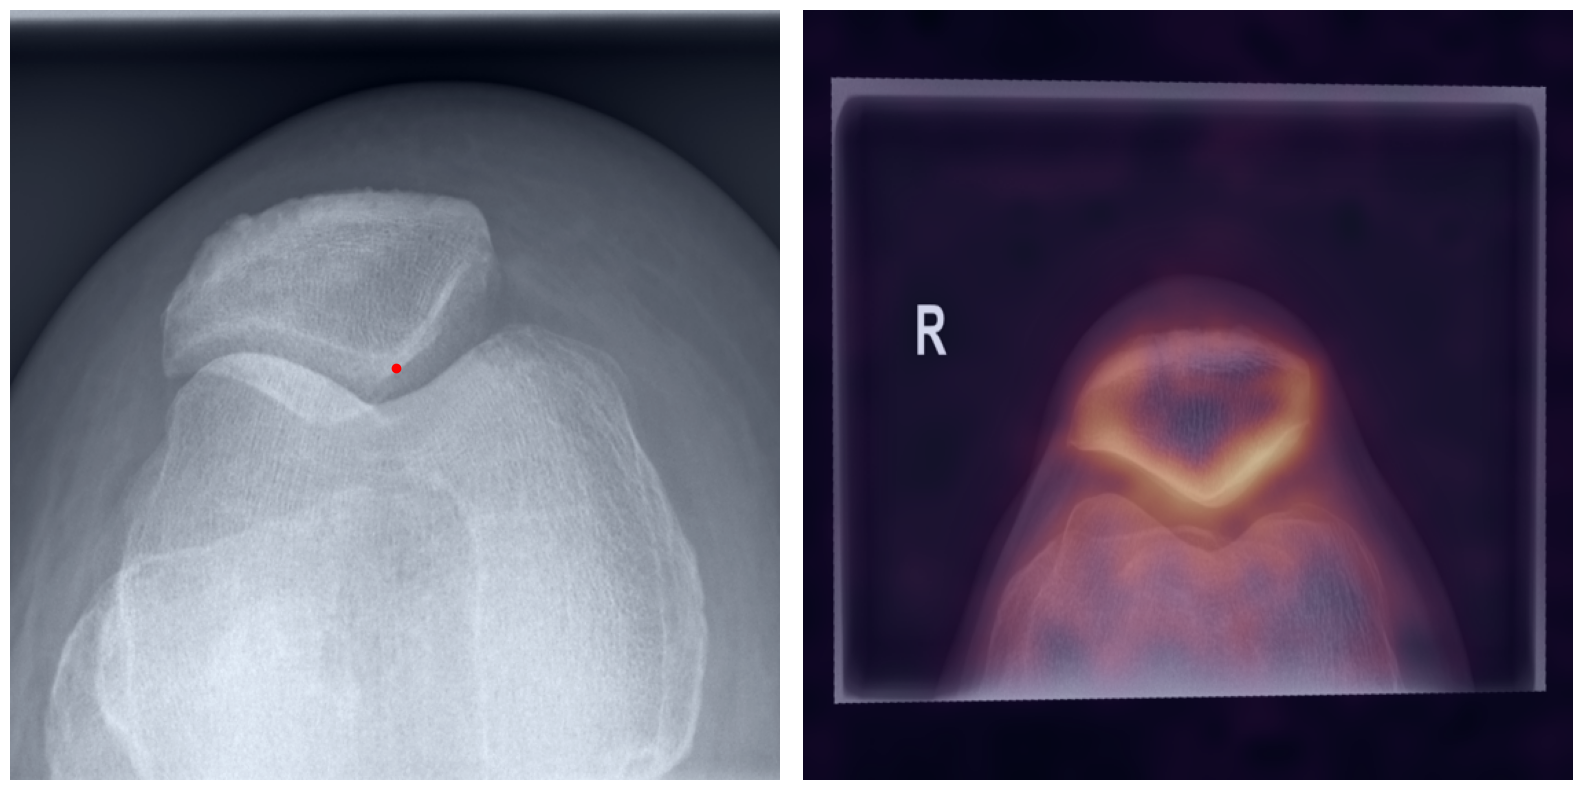

Behind the Curtain: Visualizing the Inner Workings

The process of establishing a dense match between two images relies on abstract feature representations for each position in both the reference and target images. To better understand which information is encoded by the AI, we examined the feature similarities between a specific position within the reference image and the entire target image. Our findings show that the AI captures both semantic and texture features. The matching process utilizes this encoded information, along with precise positional data, to create a reliable mapping between the images.

Hover your mouse over the image to stop automatic transitions.